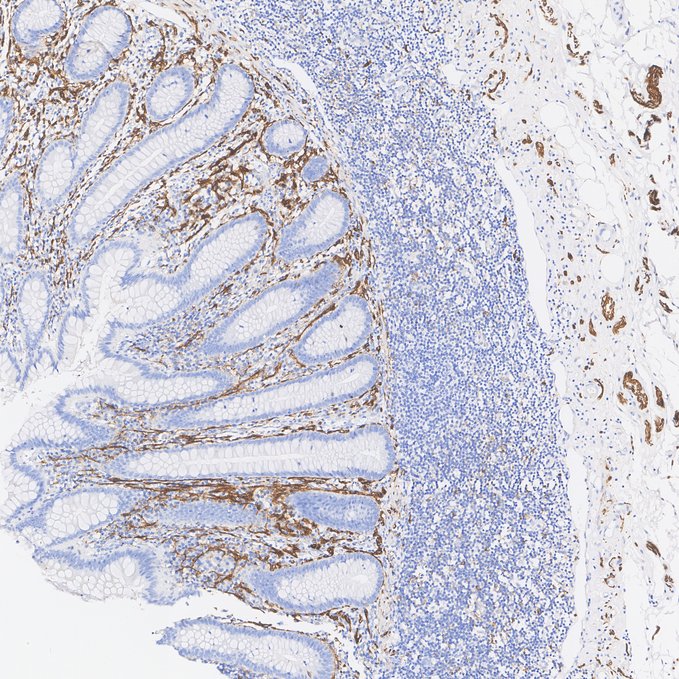

Immunohistochemical analysis of paraffin-embedded human appendix tissue with Rabbit anti-NCAM1 / CD56 antibody (HA723041) at 1/10,000 dilution.

The section was pre-treated using heat mediated antigen retrieval with Tris-EDTA buffer (pH 9.0) for 20 minutes. The tissues were blocked in 1% BSA for 20 minutes at room temperature, washed with ddH2O and PBS, and then probed with the primary antibody (HA723041) at 1/10,000 dilution for 1 hour at room temperature. The detection was performed using an HRP conjugated compact polymer system. DAB was used as the chromogen. Tissues were counterstained with hematoxylin and mounted with DPX.